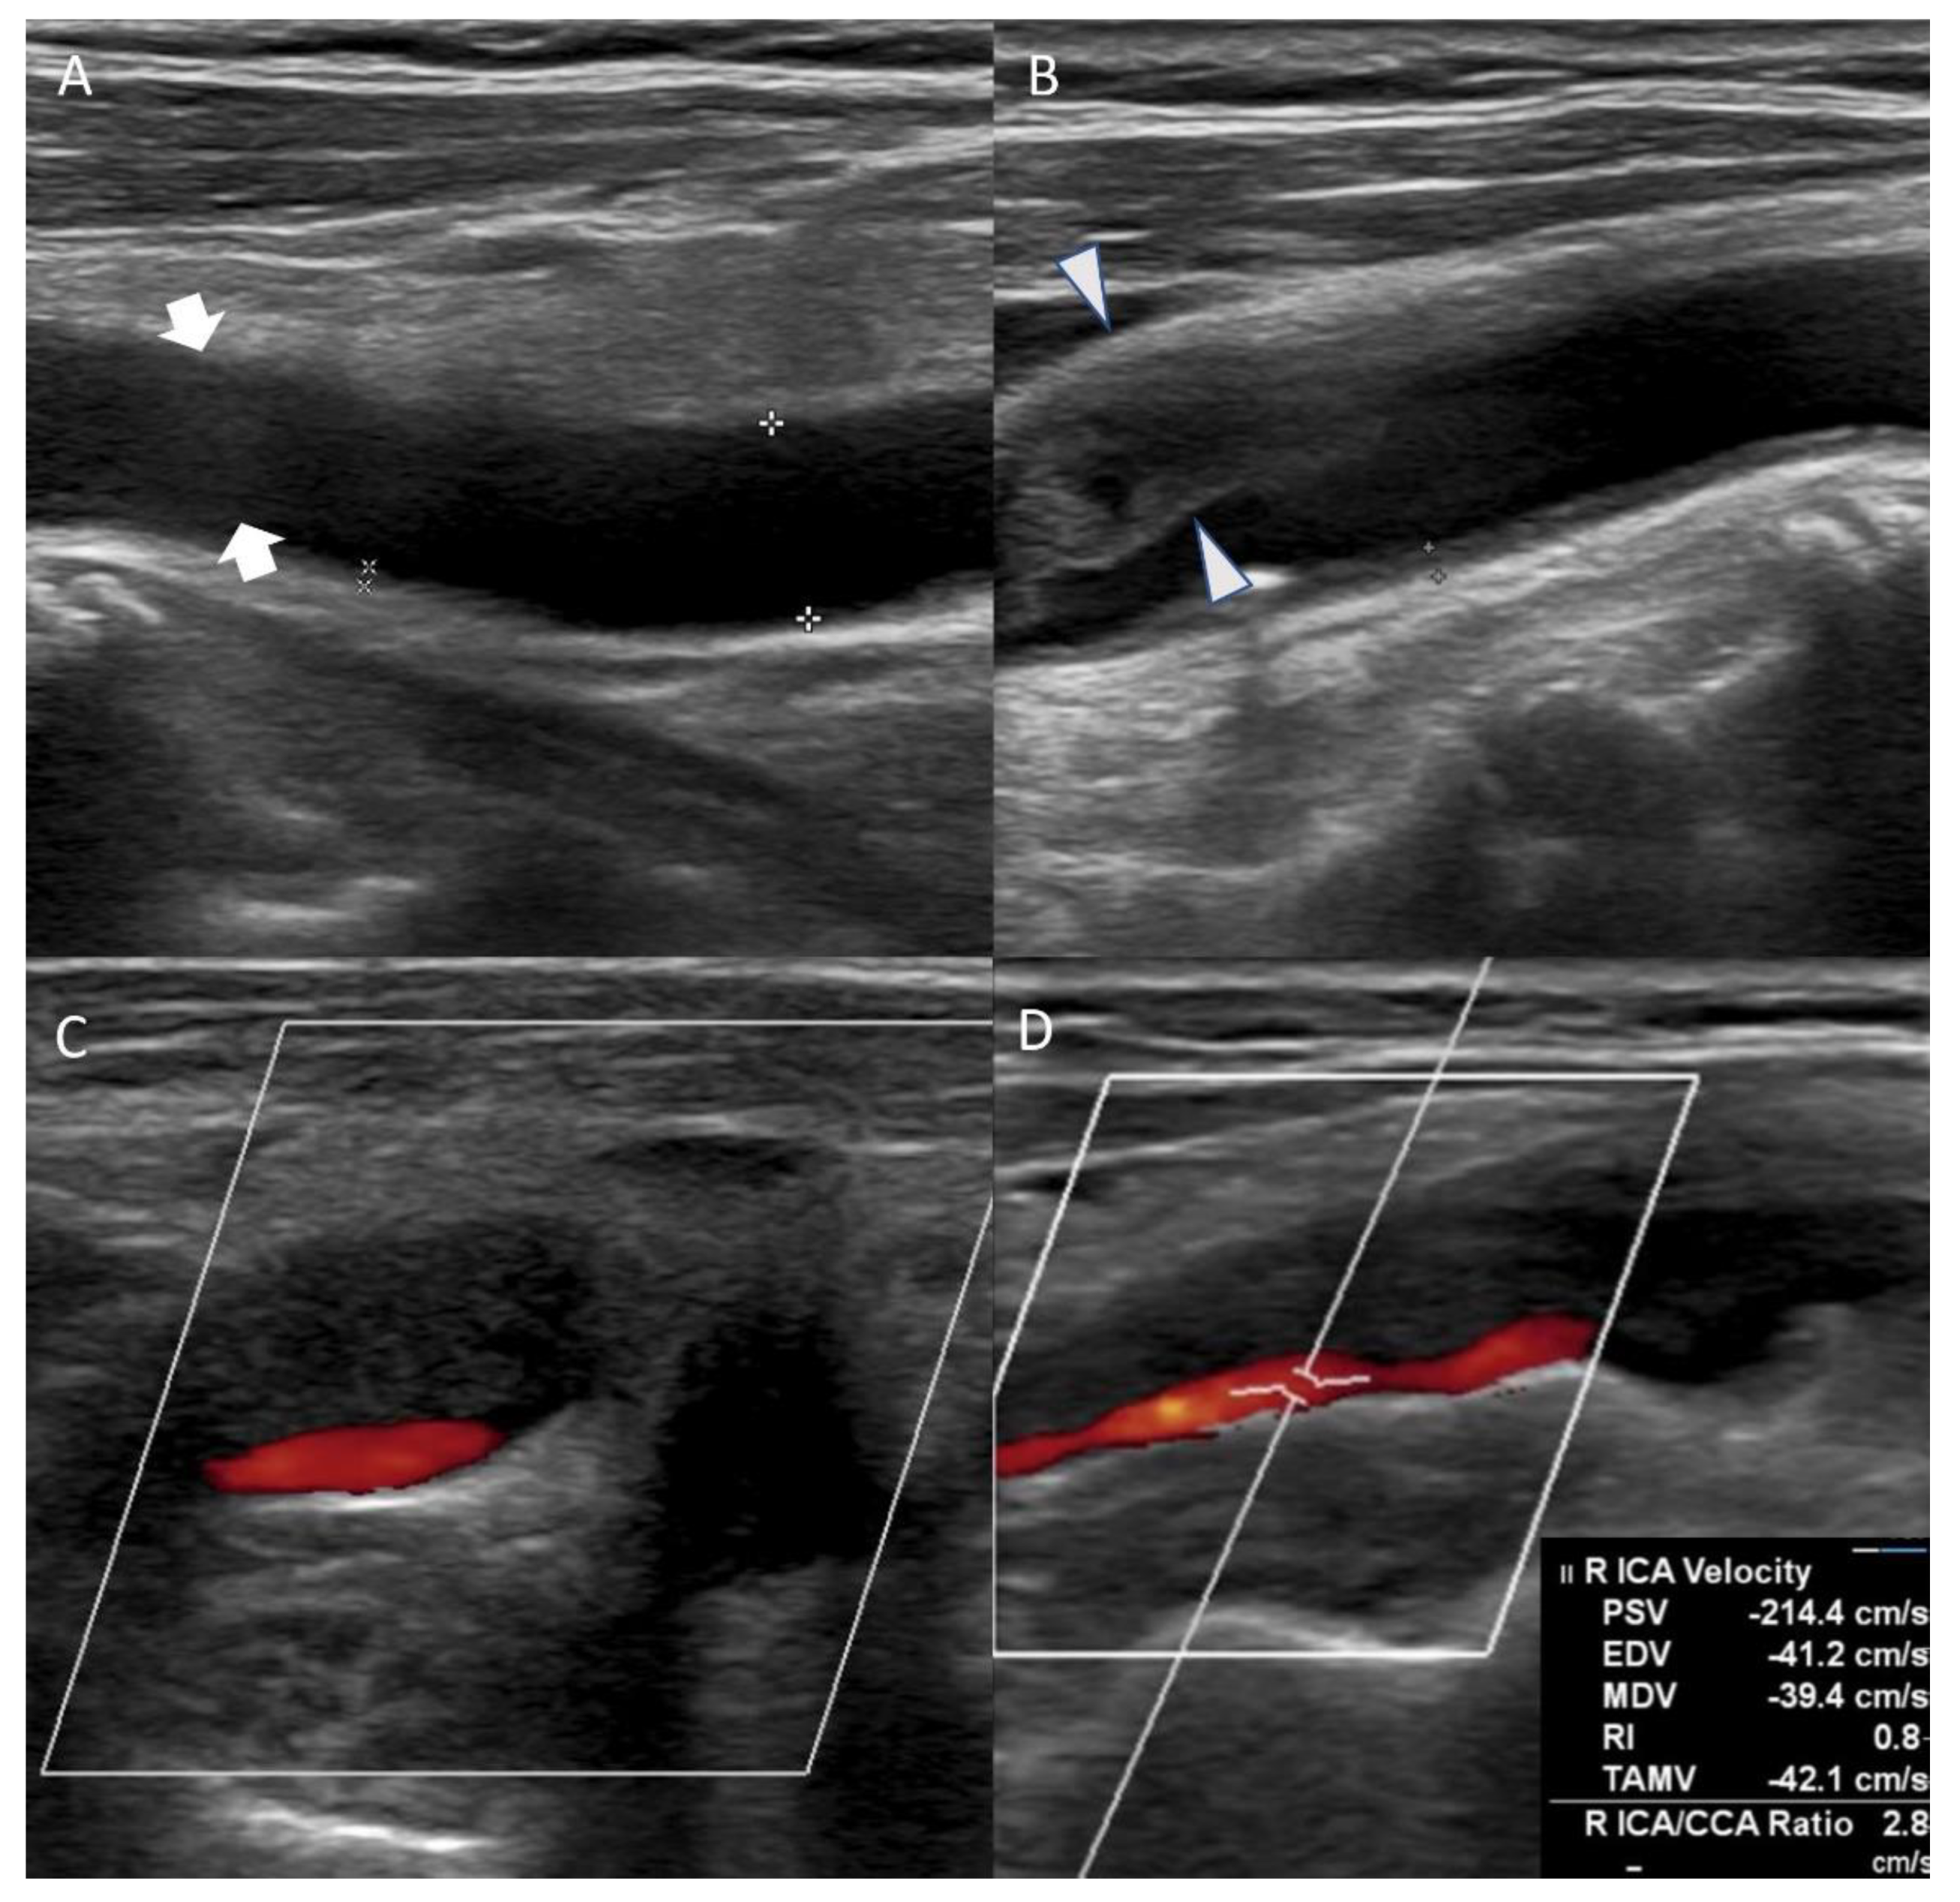

On the eighth day of hospitalization, the patient complained of dyspnea. Pleural effusion in the right lung was confirmed by follow-up chest X-ray, and the management for pleural effusion was initiated. On the eleventh day of hospitalization, carotid duplex ultrasonography showed extensive stenosis from the right carotid artery bulb to the proximal ICA (Figure 2). Peak systolic velocity (PSV) measured at the site of ICA stenosis was 214.4 cm/s, indicating moderate to severe grade stenosis (Figure 2). Although the patient needed (DSA) and carotid artery stenting to manage the symptomatic CAS, these procedures were delayed to the sixteenth day of hospitalization because of her aggravated general condition due to pleural effusion. On the right ICA angiogram of the DSA, the previously confirmed moderate to severe stenosis had almost regressed. Only mild stenosis with ulcerative plaque was observed (Figure 1D, 15% of the North American Symptomatic Carotid Endarterectomy Trial, NASCET). Therefore, carotid stenting was not performed, and we focused on acute stroke management. There were no additional lesions on the follow-up MRI. The patient was subsequently discharged without significant problems. One month after discharge, the patient’s lipid profile improved and the results are as follows: LDL cholesterol (116 mg/dL), total cholesterol (195 mg/dL), triglyceride (155 mg/dL), and HDL cholesterol (48 mg/dL).

Figure 2.

Carotid duplex ultrasonography conducted on the eleventh day of hospitalization showed echolucent (hypoechoic) plaque of right common carotid artery ((A), arrow) and extensive stenosis of right carotid artery bulb ((B), arrowhead). Axial view of the carotid artery bulb presented heterogeneous plaque suggesting lipid and calcification (C). Echolucent (hypoechoic) plaque that occluded right proximal internal carotid artery was observed, and peak systolic velocity of the internal carotid artery (ICA) stenosis site was 214.4 cm/s (D).